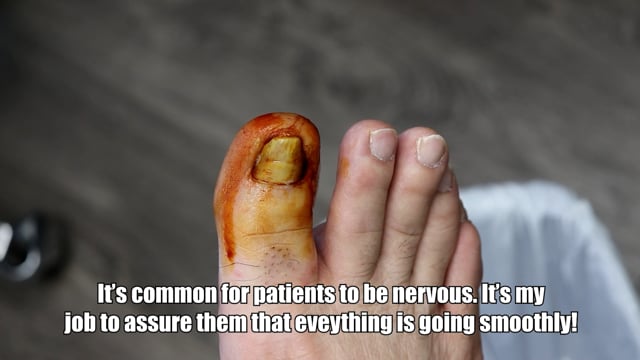

Removing an unbelievable infected ingrown toenail!!!

Ingrown Removal